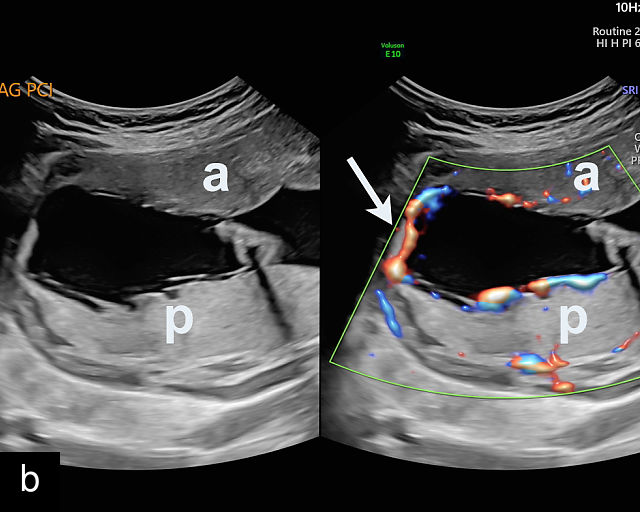

4

Accessory placental lobes. (a) Color Doppler transabdominal ultrasound image depicting a bilobed placenta with an anterior (a) and posterior (p) lobe, into which the cord inserts. (b) Grayscale ultrasound with color flow Doppler showing a bilobed placenta with anterior (a) and posterior (p) lobes. Color flow Doppler shows unprotected fetal vessels traversing the membranes between the lobes (arrow). (c) Grayscale ultrasound showing a bilobed placenta with anterior (a) and posterior (p) lobes.

The sonographic features of a bilobed or succenturiate-lobed placenta include the presence of two distinct placental masses, typically one anterior and the other posterior, which may vary in size or be of equal size.21,22,23,24,26,31,32,33 These masses are connected by blood vessels, which can be visualized using color flow Doppler (Figure 4).28

The placental cord insertion in these cases is often velamentous and may be located between the placental lobes (Figure 4b; Video 2). In rare cases, furcate insertion, in which the cord vessels branch before reaching the placental tissue, between the lobes has been reported.24

Accessory placental lobes. (a) Grayscale (left) and color flow Doppler (right) ultrasound of bilobed placenta with cord insertion between the placental lobes. The cord insertion is marginal into the anterior lobe and unprotected vessels run through the membranes for a short distance into the posterior placental lobe. (b) Grayscale ultrasound showing a bilobed placenta.